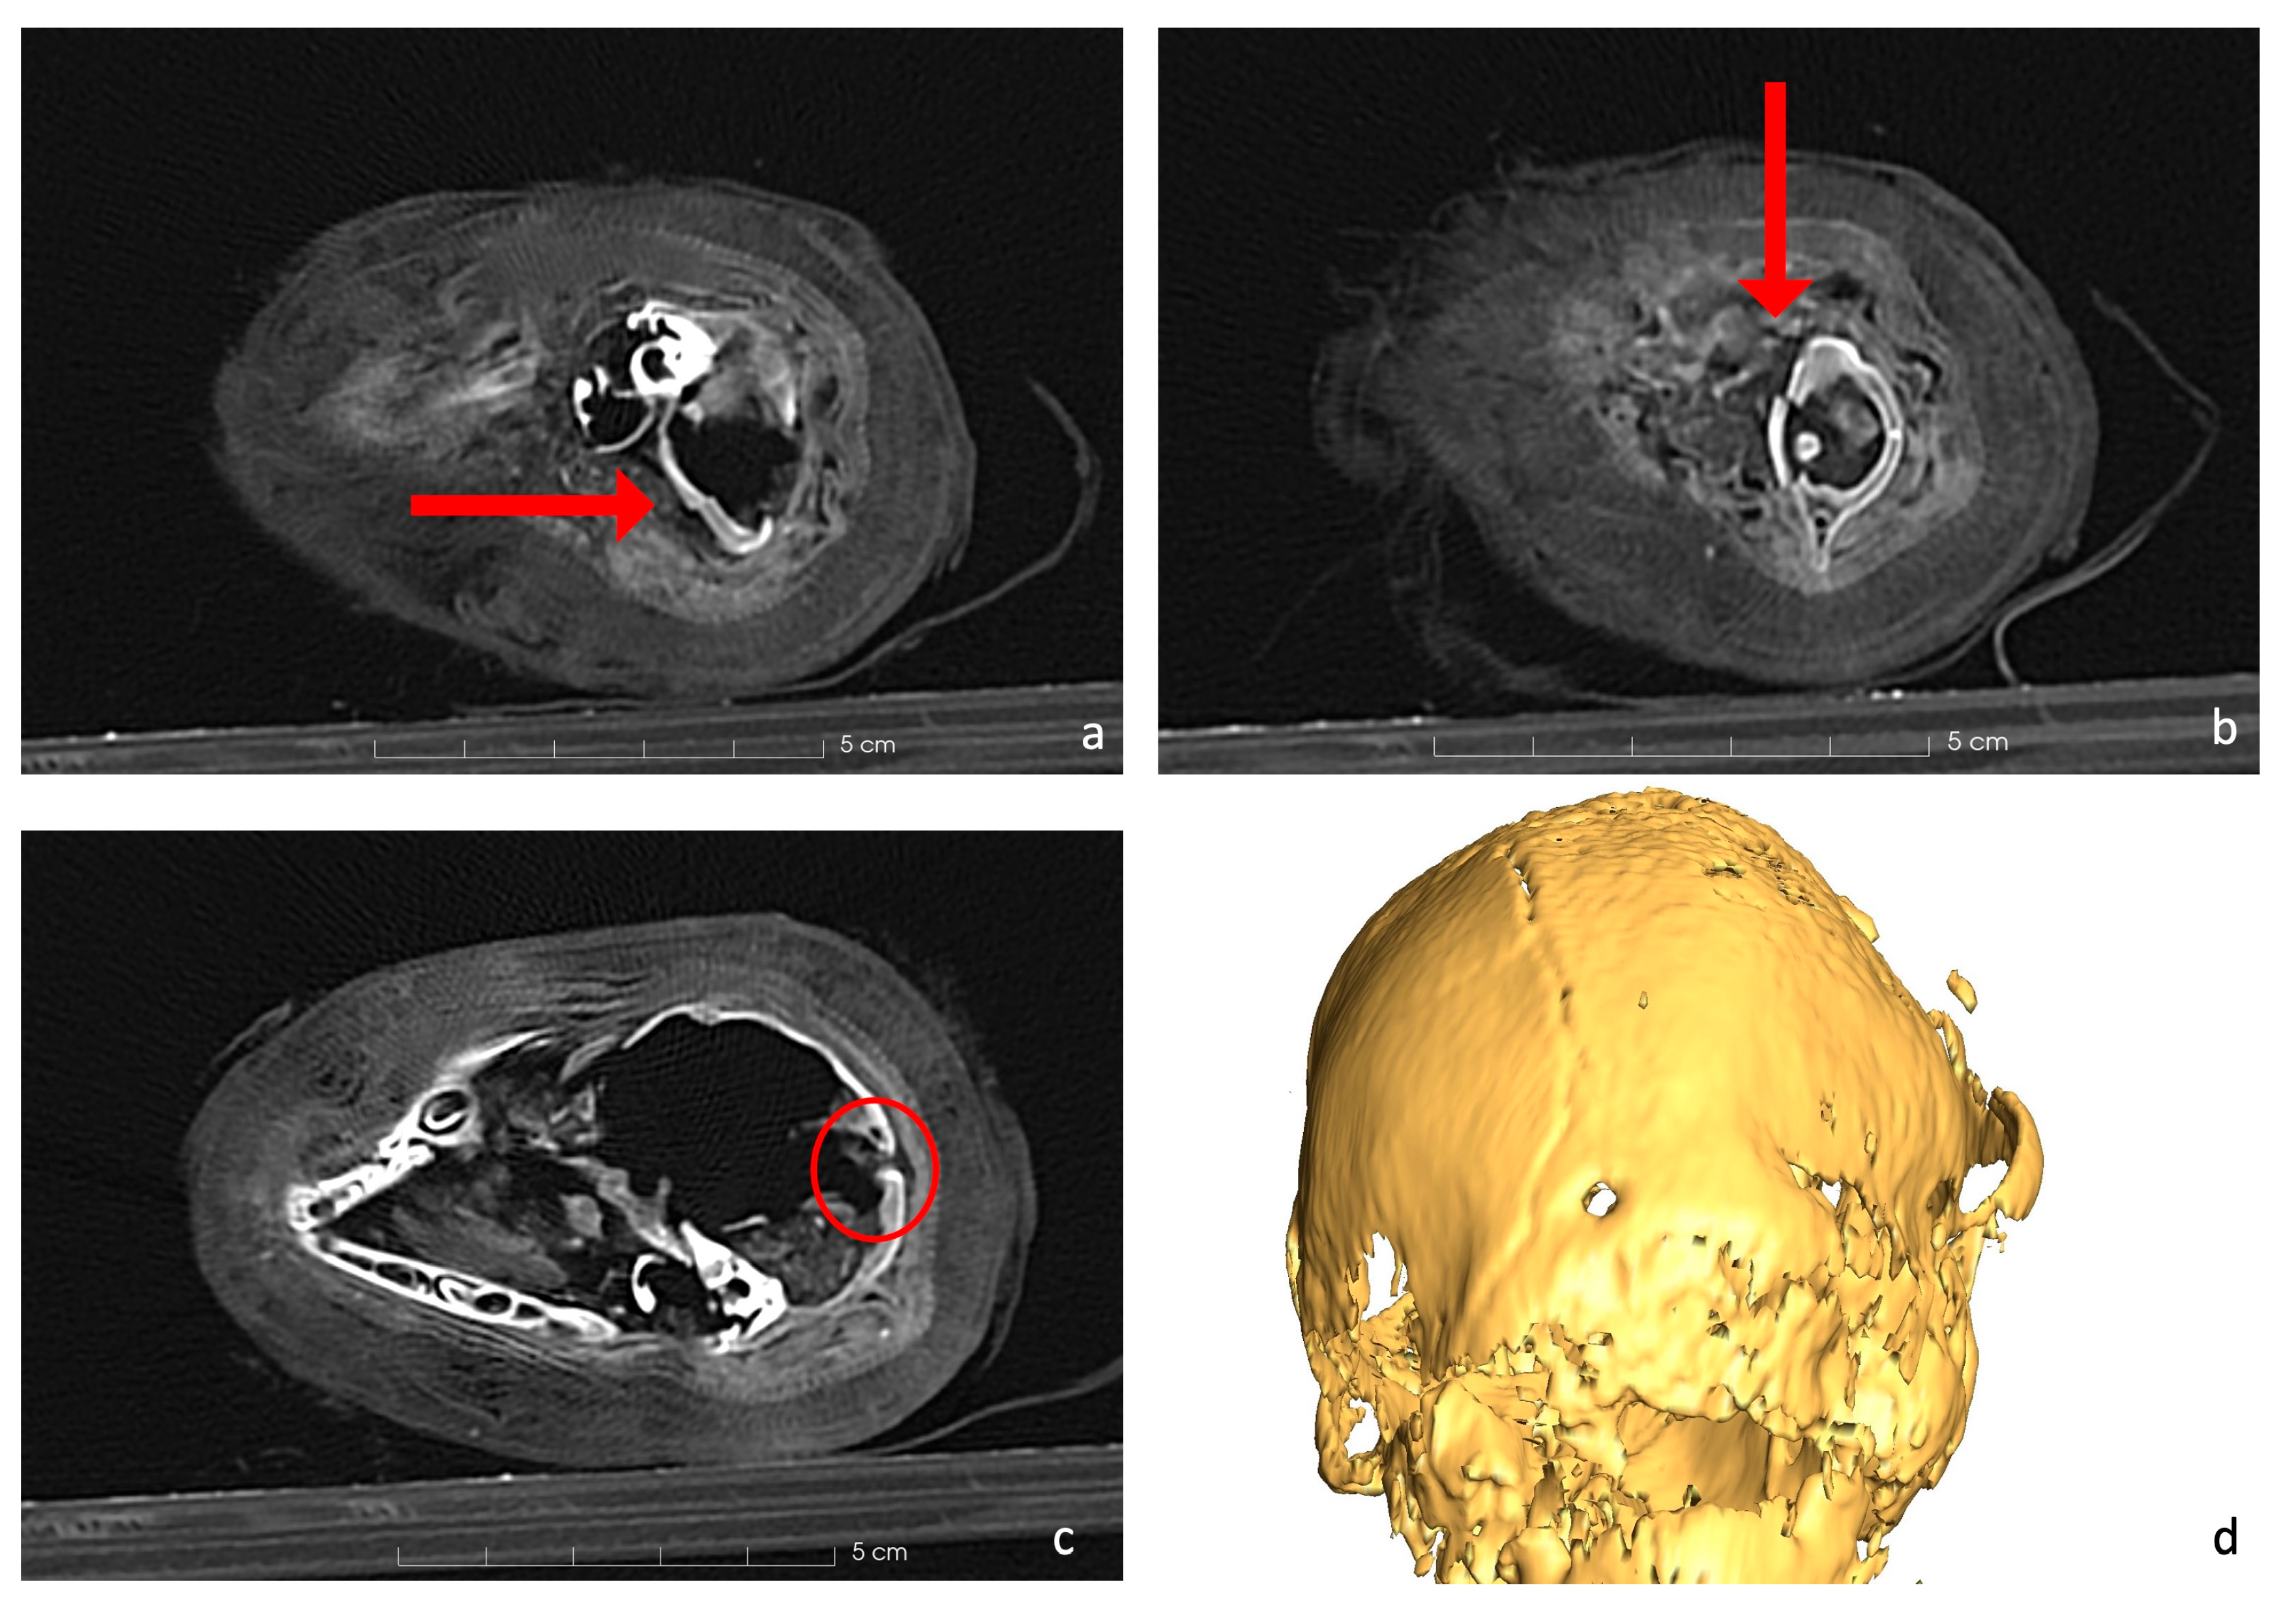

Deeper analyses revealed several bone fractures. The cranial region showed a significant fracture. The sides of the foramen magnum and the first cervical vertebra appeared discontinuous and damaged; additionally, the atlas had a clear fracture in the ventral side, where the arch of the vertebra is separated from the rest of it (Figure 5a,b).

Figure 5.

The head of the cat mummy. (a) Axial CT of the foramen magnum depicts a discontinuity of the occipital bone compatible with the fracture of the atlas (b), where the ventral arch is separated from the rest of the body (red arrow, axial CT scan). (c) Axial CT scan of the foramen in the occipital bone (2 mm). (d) 3D rendering of the skull with the foramen.

Furthermore, the occipital bone of the cat’s skull featured a centrally located posterior rounded foramen measuring 2 mm in diameter (Figure 5c).

Previous research on mummified cats has shown that a common method to sacrifice young cats was to break their necks by twisting them or hitting them on their head [46,48,51]. These procedures left prominent marks near the cervical vertebrae and occipital portion of the skull [48]. Based on a comparison between our cat mummy and cases reported in the literature [19,46,48], it is feasible to conclude that the death may be attributed to a neck dislocation with visible fractures, as shown in Figure 5a,b.

Additionally, the CT scans highlighted the presence of a perfectly rounded and symmetric foramen in the occipital bone (Figure 5c,d). Various hypotheses have been proposed regarding its origin, suggesting it may be related to a traumatic injury, such as a small perforation by a small tool, given its 2 mm dimension, or it could represent an anatomical feature of the skull that occasionally forms. However, the exact nature of this foramen cannot be definitively ascertained from the CT scan alone, as it requires more detailed analysis for a thorough understanding.